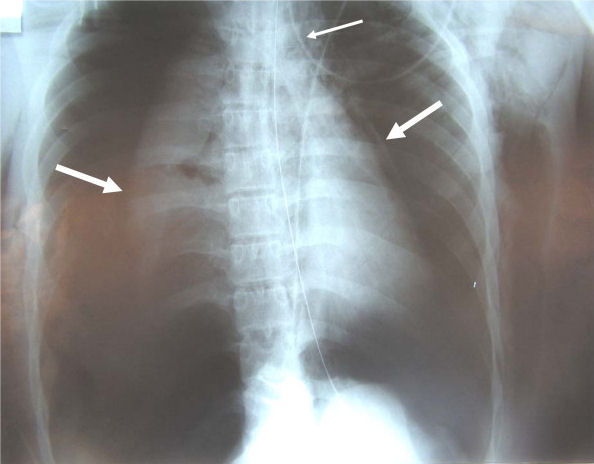

back tracheobronchial injury

Source: Le Guen et al. Critical Care 2007 11:R94 doi:10.1186/cc6109